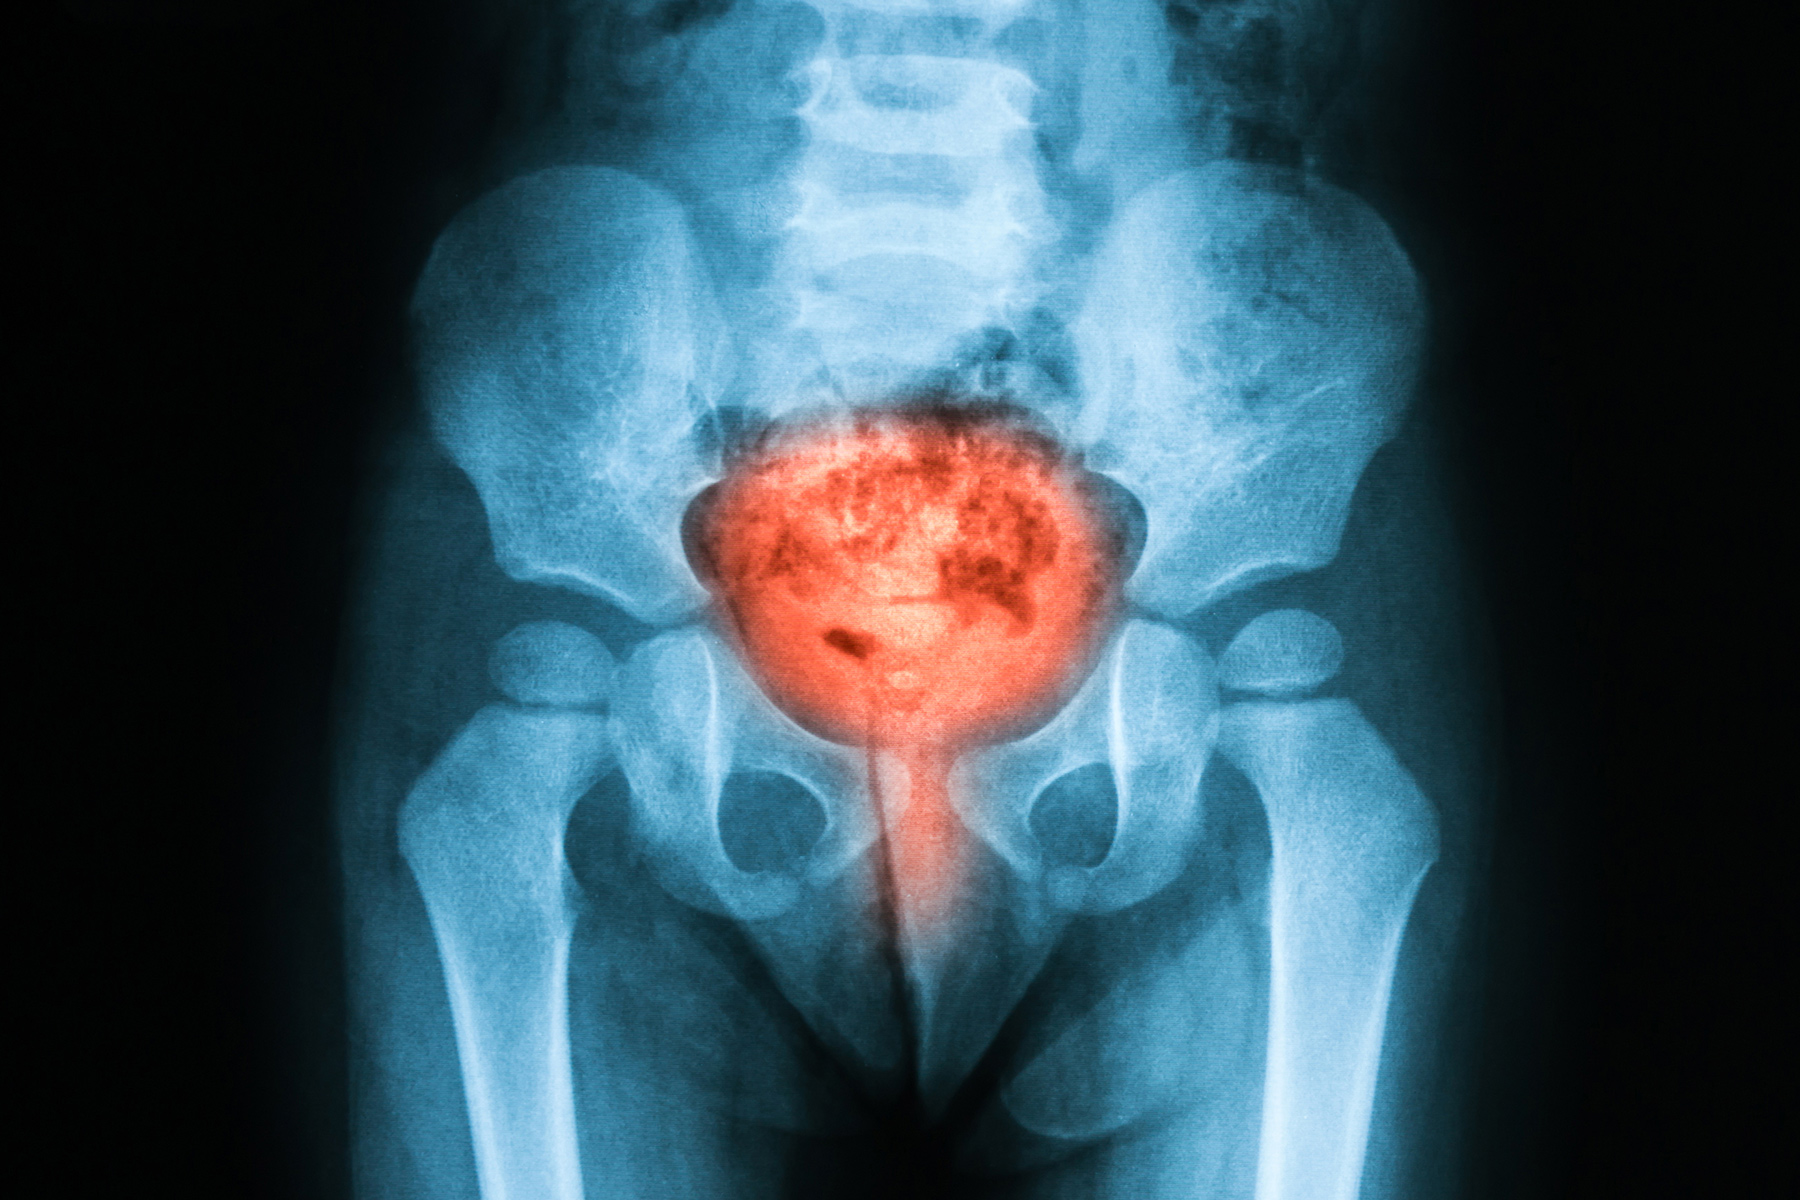

肾结石

矿物质和盐分在肾脏中形成微小石块。通常会觉得自己老想去洗手间,但尿尿并不多。可能会出现恶心,发烧,发冷和身体背部的一侧会严重疼痛,像波浪一样延伸到腹股沟。肥胖,脱水,高蛋白饮食和有家族病史的人患肾结石的可能性更高。结石可能会自行脱落,或者可能需要进行手术。

肿瘤

恶性和良性肿瘤都可以导致尿频,因为它们会占用膀胱内或膀胱周围的更多空间。如果尿液带血往往提示肿瘤的可能。如果下腹部有一个肿块,要及时就医。

前列腺

男性有一个核桃大小的腺体,称为前列腺,在25岁以后可以长大。前列腺增大会使排尿无力,不均匀和尿频,有时突然就要去洗手间。前列腺癌的发病率非常低,不用过于担心,至于前列腺肥大,是完全可以治疗的。